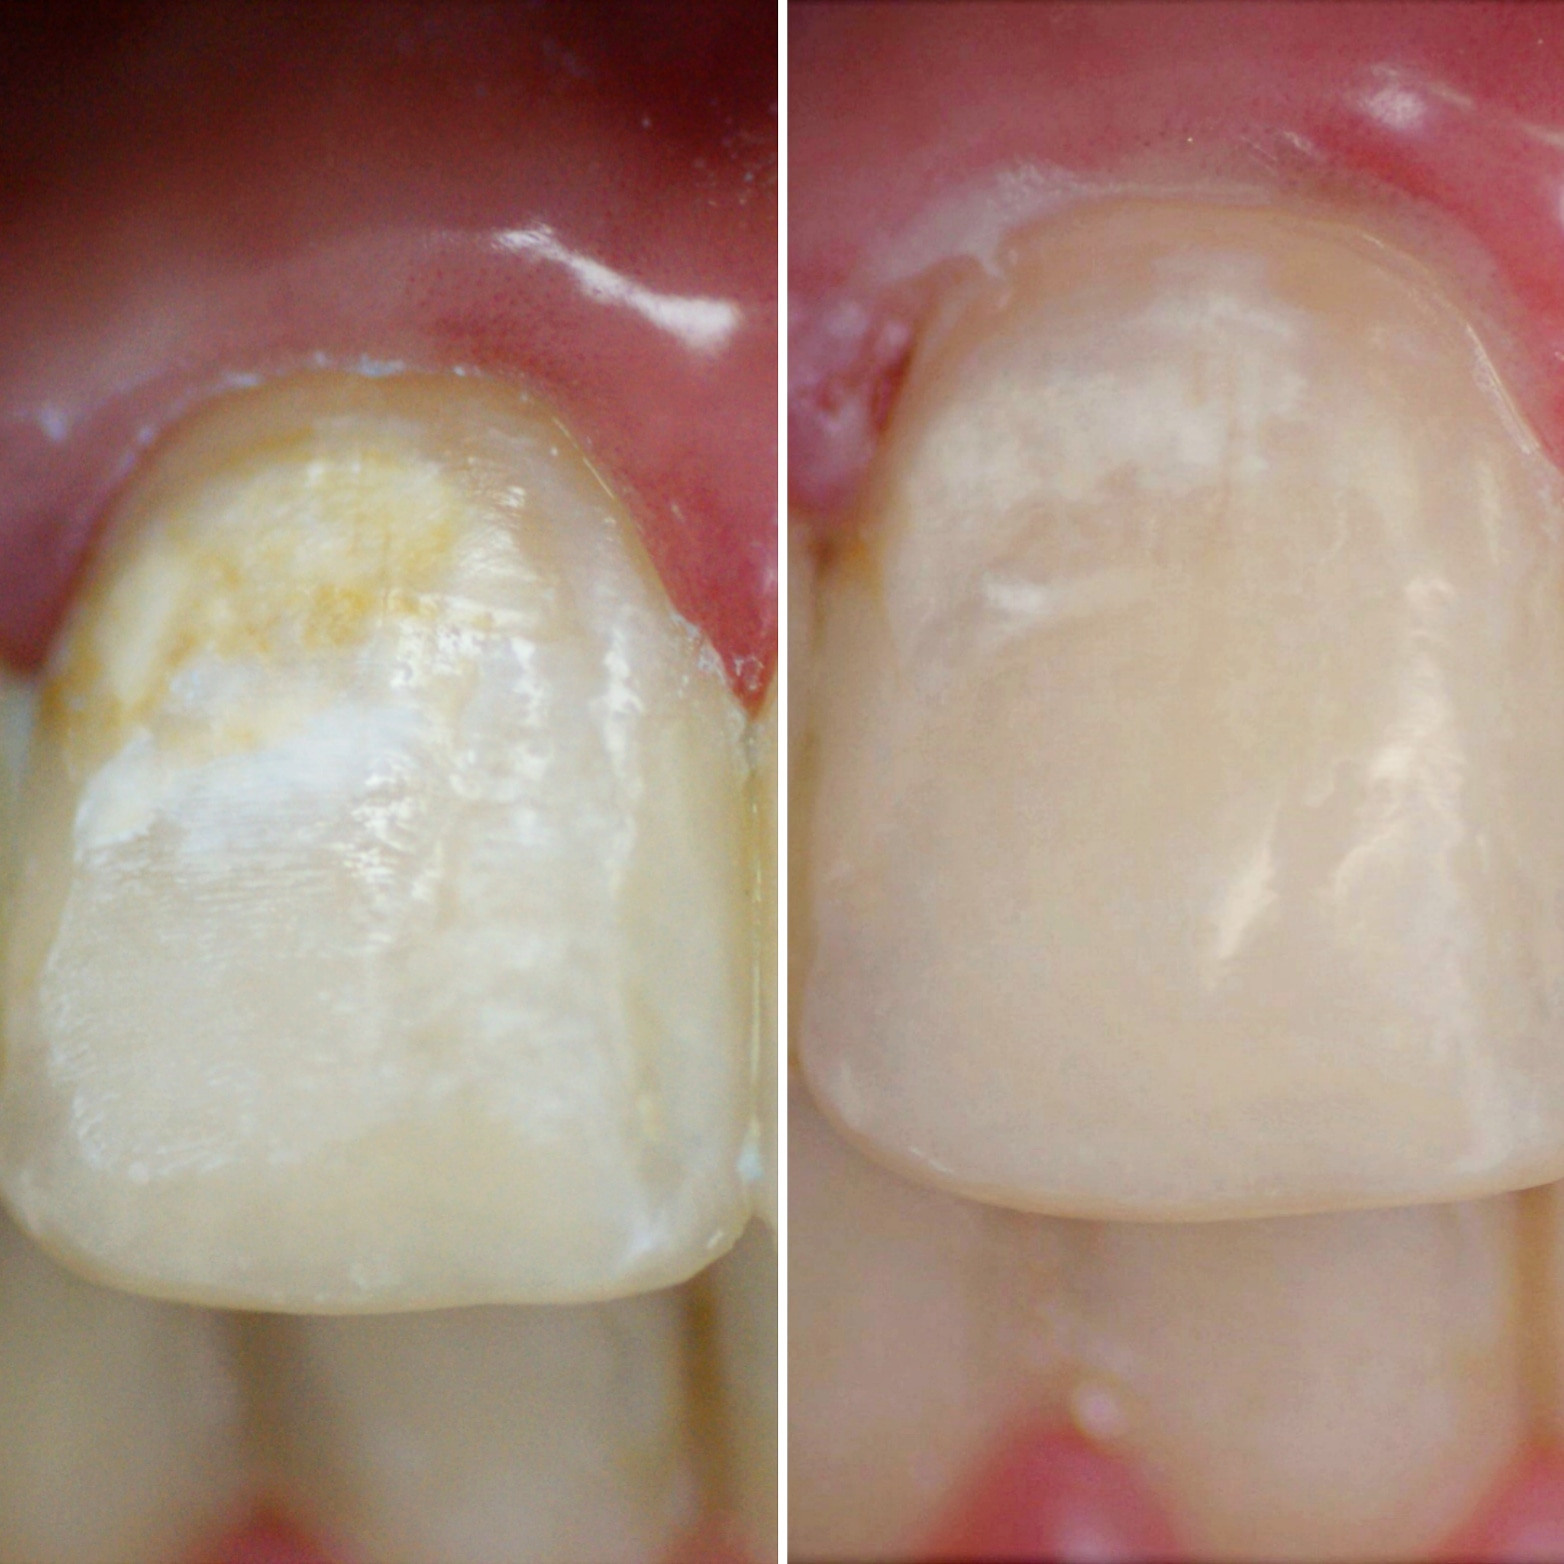

Дома с ORMCO. Марафон прямых эфиров👍

✔Во время длительного ортодонтического лечения гигиена затруднена из-за наличия во рту брекетов, дуг, резинок и тд. ✔ Если гигиена не поддерживается на должном уровне, на эмали зубов образуется начальный кариес в виде белых (желтоватых) пятен, который может превратиться в полости или “дырки” (на левой фотографии).✔ Обращаю Ваше внимание, что брекеты зубы не портят! Отсутствие гигиены портит зубы! ✔На правой фотографии современное решение этой проблемы – лечение кариеса без сверления, метод инфильтрации кариеса ICON.